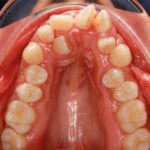

L’espansione del palato, come e quando attuarla

Rappresenta senza dubbio il “gold standard” nei casi di morso crociato in pazienti in crescita, tuttavia è possibile effettuare tale terapia anche in altre circostanze. Lo spiega Alberto Caprioglio, direttore della Scuola di specializzazione in Ortognatodonzia presso l’Università degli Studi dell’Insubria, rispondendo ai dubbi di una giovane odontoiatra.

L’espansore rapido tipo Haas